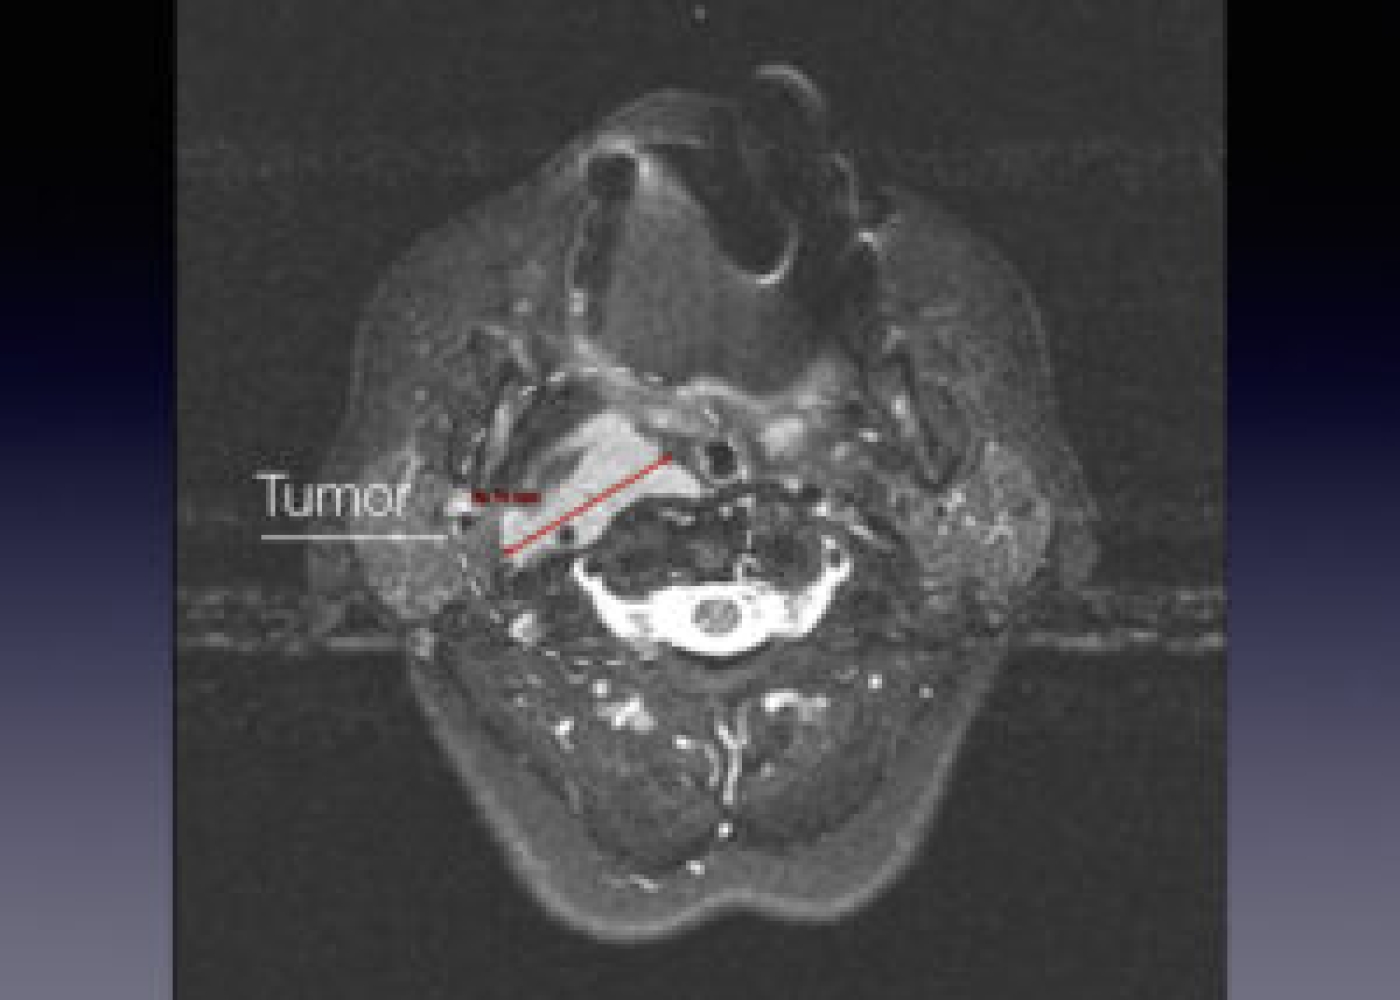

Պացիենտի խոսքով՝ գանգատներն ի հայտ են եկել մոտ 1,5 տարի առաջ և հաջորդիվ գոյացության չափերը զգալի մեծացել են: Հետազոտման ժամանակ աջից պարանոցի քնային եռանկյունում հայտնաբերվել է հստակ սահմաններով մոտ 4սմ տրամագծով անցավ գոյացություն:

Կլինիկոպարակլինիկական հետազոտությունների արդյունքում ախտորոշվել է քնային զարկերակի բիֆուրկացիայի անգիոմիոմատոզ համարտոմա աջից, որը ճնշում էր արտաքին քնային զարկերակը: